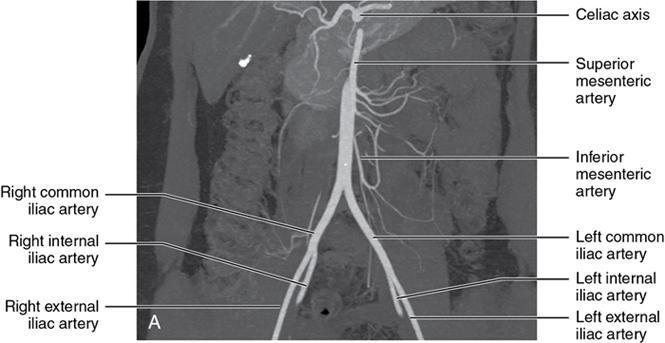

CROSS SECTIONAL ANATOMY OF ABDOMEN Satya Jha NORMAL ANATOMY OF ABDOMEN AND PELVIS Amandeep Singh The two major surfaces: The anterior and posterior layers of the coronary ligament converge on bare area (not covered by peritoneum). Its right and left margins form the right and left triangular ligaments. The right triangular ligament extends toward the diaphragm and separates right subphrenic space from right subhepatic space. The left triangular ligament gives tracts extending to the diaphragm and falciform ligament and does not compartmentalize the left subphrenic space. Ligamentum teres or the obliterated umblical vein is contained in falciform ligament which attaches the liver to anterior abdominal wall. The main portal vein, the proper hepatic artery and the common bile duct are contained within investing peritoneal folds of hepatoduodenal ligament at the porta hepatis (Fig. 7.2.2.1). Liver is divided into eight segments which are functionally independent and have their own vascular supply and biliary drainage. Arterial circulation: The branches of the hepatic artery accompanying the portal veins. Hepatic venous system: The right, middle, and left hepatic veins draining into IVC (Figs. 7.2.2.2 and 7.2.2.3). The gallbladder is a blind pear-shaped muscular membranous sac which is an embryologic derivative of the foregut, is a pouch lying along the undersurface of the liver. The gallbladder fossa is located in the plane of the interlobar fissure, which lies between the right and left hepatic lobes. Its major function is to store and concentrate bile which is produced by the liver. It measures approximately 4 cm in diameter when it is normally distended. Gallbladder is a smaller tubular structure in contracted state. The normal gallbladder wall thickness ranges from 1 to 3 mm. The gallbladder is divided into the fundus, body and neck. Infundibulum is present in the region of neck of the gallbladder, which is called the Hartmann pouch, where gallstones are usually impacted. Intrahepatic biliary radicles (IHBRs) scattered throughout the liver get confluent towards the hilum. They unite to form the right and left main hepatic ducts which further unite to form common hepatic duct (CHD) at the hilum. Common bile duct is formed by the union of cystic duct with common hepatic duct. The main pancreatic duct is joined with the common bile duct to form the ampulla of Vater at the major duodenal papilla (Figs. 7.2.2.4 and 7.2.2.5). Pancreas is located in anterior pararenal space of retroperitoneum anterior to perirenal (Gerota’s) fascia and posterior to parietal peritoneum. It is divided into head, uncinate process, neck, body and tail from right to left. Pancreas lies anterior to portal vein, which marks the point of transition between the body and neck. The region between head of pancreas and second and third parts of duodenum is known as the pancreatic groove. In postnephrectomy cases or with agenesis of kidney or ectopic kidney, pancreas moves posteriorly to partially fill in the empty renal fossa; its soft tissue density should not be mistaken for recurrent tumour. It is located in the pancreatic groove and is bounded superiorly by the duodenal bulb, laterally by second portion of duodenum, inferiorly by third portion of duodenum, medially by superior mesenteric vein and anterior to inferior vena cava. It is a wedge or wedge shaped lying posterior to superior mesenteric artery and vein. It is an imaginary junction between the head and body and lies directly over the junction of the splenic vein and superior mesenteric vein. It is located posterior to the lesser sac and anterior to the aorta, left adrenal gland, left kidney, and renal vessels and runs obliquely upward to the left of the superior mesenteric vessels. It is situated median to the colonic flexure and anterior to the left kidney. It is located in close proximity to the splenic hilum without a notable relation with the body of pancreas. It is seen anterior to the left kidney and median to the colonic flexure. The distal part of the tail passes between the peritoneal layers of the splenorenal ligament (Fig. 7.2.2.6 and 7.2.2.7).